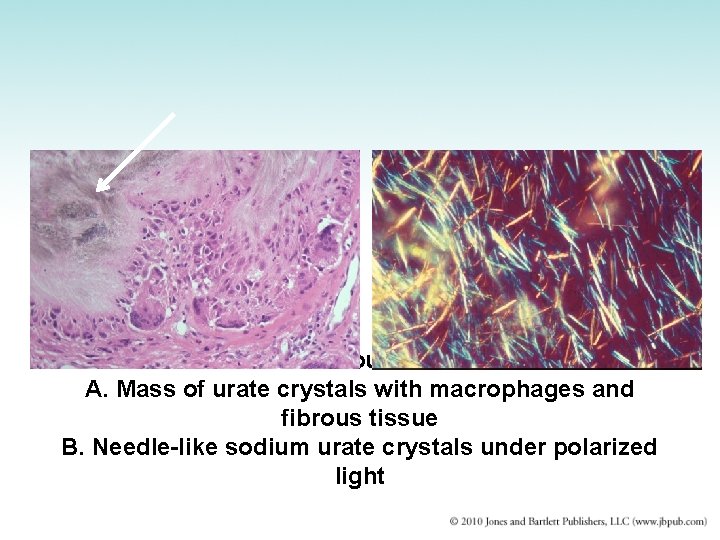

Gout • Disorder of purine metabolism – Uric acid: an insoluble end-product of purine metabolism – Acute episodes caused by precipitation of uric acid crystals in joint fluid – Uric acid stones also may form within kidney and lower urinary tract • Urate nephropathy: urate deposits plug tubules and damage kidneys – Treatment: diet and drugs that lower uric acid

Gout

Gout A. Mass of urate crystals with macrophages and fibrous tissue B. Needle-like sodium urate crystals under polarized light